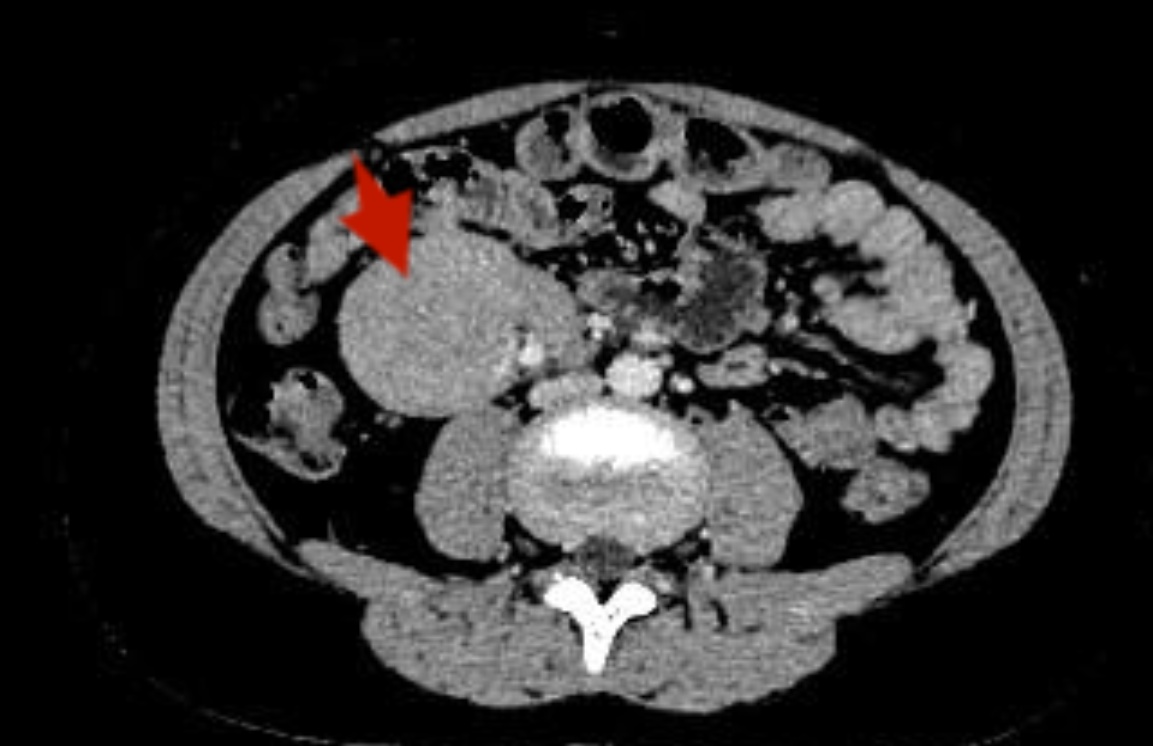

患儿男,年龄11岁3个月。因“阵发性脐周腹痛1周”于2025年4月1日入我院就诊。患儿腹痛持续时间不等,性质为隐痛,平素无发热、头晕、头痛,无恶心、呕吐,无腹泻便秘、小便发黄等症状,体重、体力无明显下降。既往贫血3年,定期复查血常规:血红蛋白90~105 g/L波动,长期补充铁剂无改善。否认相关病毒感染史、传染病史等其他病史。体格检查:神志清,精神可,面色皮肤苍白,指甲床苍白,无皮肤出血点及瘀斑。颈部、腋窝、腹股沟等全身浅表淋巴结无明显肿大,腹平坦,腹软不胀,未见胃肠型及蠕动波,移动性浊音阴性,右下腹压痛,无反跳痛,余腹无压痛及肌紧张,肝脾肋下未触及,Murphy阴性,未触及明显肿物,肠鸣音4次/分。实验室检查:血常规:血红蛋白85 g/L,血小板740 × 10^9/L,C反应蛋白25 mg/L,肝功能:白蛋白29.7g/L,白细胞介素-6:66.31 pg/ml,免疫球蛋白测定(血):抗O:>1770 IU/ml,血沉:111 mm,EB病毒衣壳抗原IgA 6.19 AU/ml,EB病毒衣壳抗原IgG > 50 AU/ml,EB病毒核抗原IgG > 50 AU/ml,HHV-8:阴性,IgG4 25.12 g/L。肿瘤标志物甲胎蛋白、癌胚抗原、糖链抗原199、神经元特异性烯醇化酶等检查指标均在正常参考范围内,Coombs实验阴性。完善超声检查:腹腔内右肾前方水平见6.0 × 4.3 × 5.6 cm低回声团块,分叶状,边界清,似有包膜,余肠系膜根部关系密切,考虑系膜来源或淋巴来源(图1)。下腹部CT平扫 + 增强提示:腹膜后可见软组织肿块影,边界清,大小约46 mm × 55 mm,增强扫描可见均匀强化,肿块周围及腹腔可见多发稍肿大淋巴结影,考虑腹膜后占位,Castleman?(图2)

Figure 1. Abdominal ultrasound examination revealed a hypoechoic mass in front of the right kidney

1. 腹部超声检查提示右肾前方低回声团块